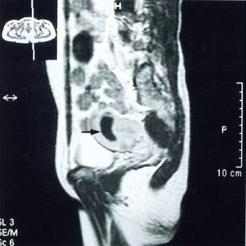

B型超聲、陰道鏡、腹腔鏡檢查、組織病理學檢查。

鑑別

1.子宮內膜異位症 子宮內膜異位症的痛經呈繼發性、進行性加重,若能觸及典型觸痛結節,有助於診斷。B型超聲檢查有助於鑑別。鑑別困難時應行腹腔鏡檢查。

2.卵巢囊腫 輸卵管卵巢囊腫需與卵巢囊腫鑑別。輸卵管卵巢囊腫除有盆腔炎病史外,腫塊呈臘腸形,囊壁較薄,周圍有粘連;而卵巢囊腫一般以圓形或橢圓形較多,周圍無粘連,活動自如。

3.卵巢癌附屬檔案炎性包塊與周圍粘連,不活動,有時易與卵巢癌相混淆,慢性炎性包塊多為囊性;而卵巢癌包塊多為實性,較硬,表面不規則,子宮直腸窩可捫及質硬的結節,常有腹水,患者一般情況較差,B型超聲檢查有助於鑑別。診斷有困難時,可藉助於腹腔鏡檢查或病理活體組織檢查。